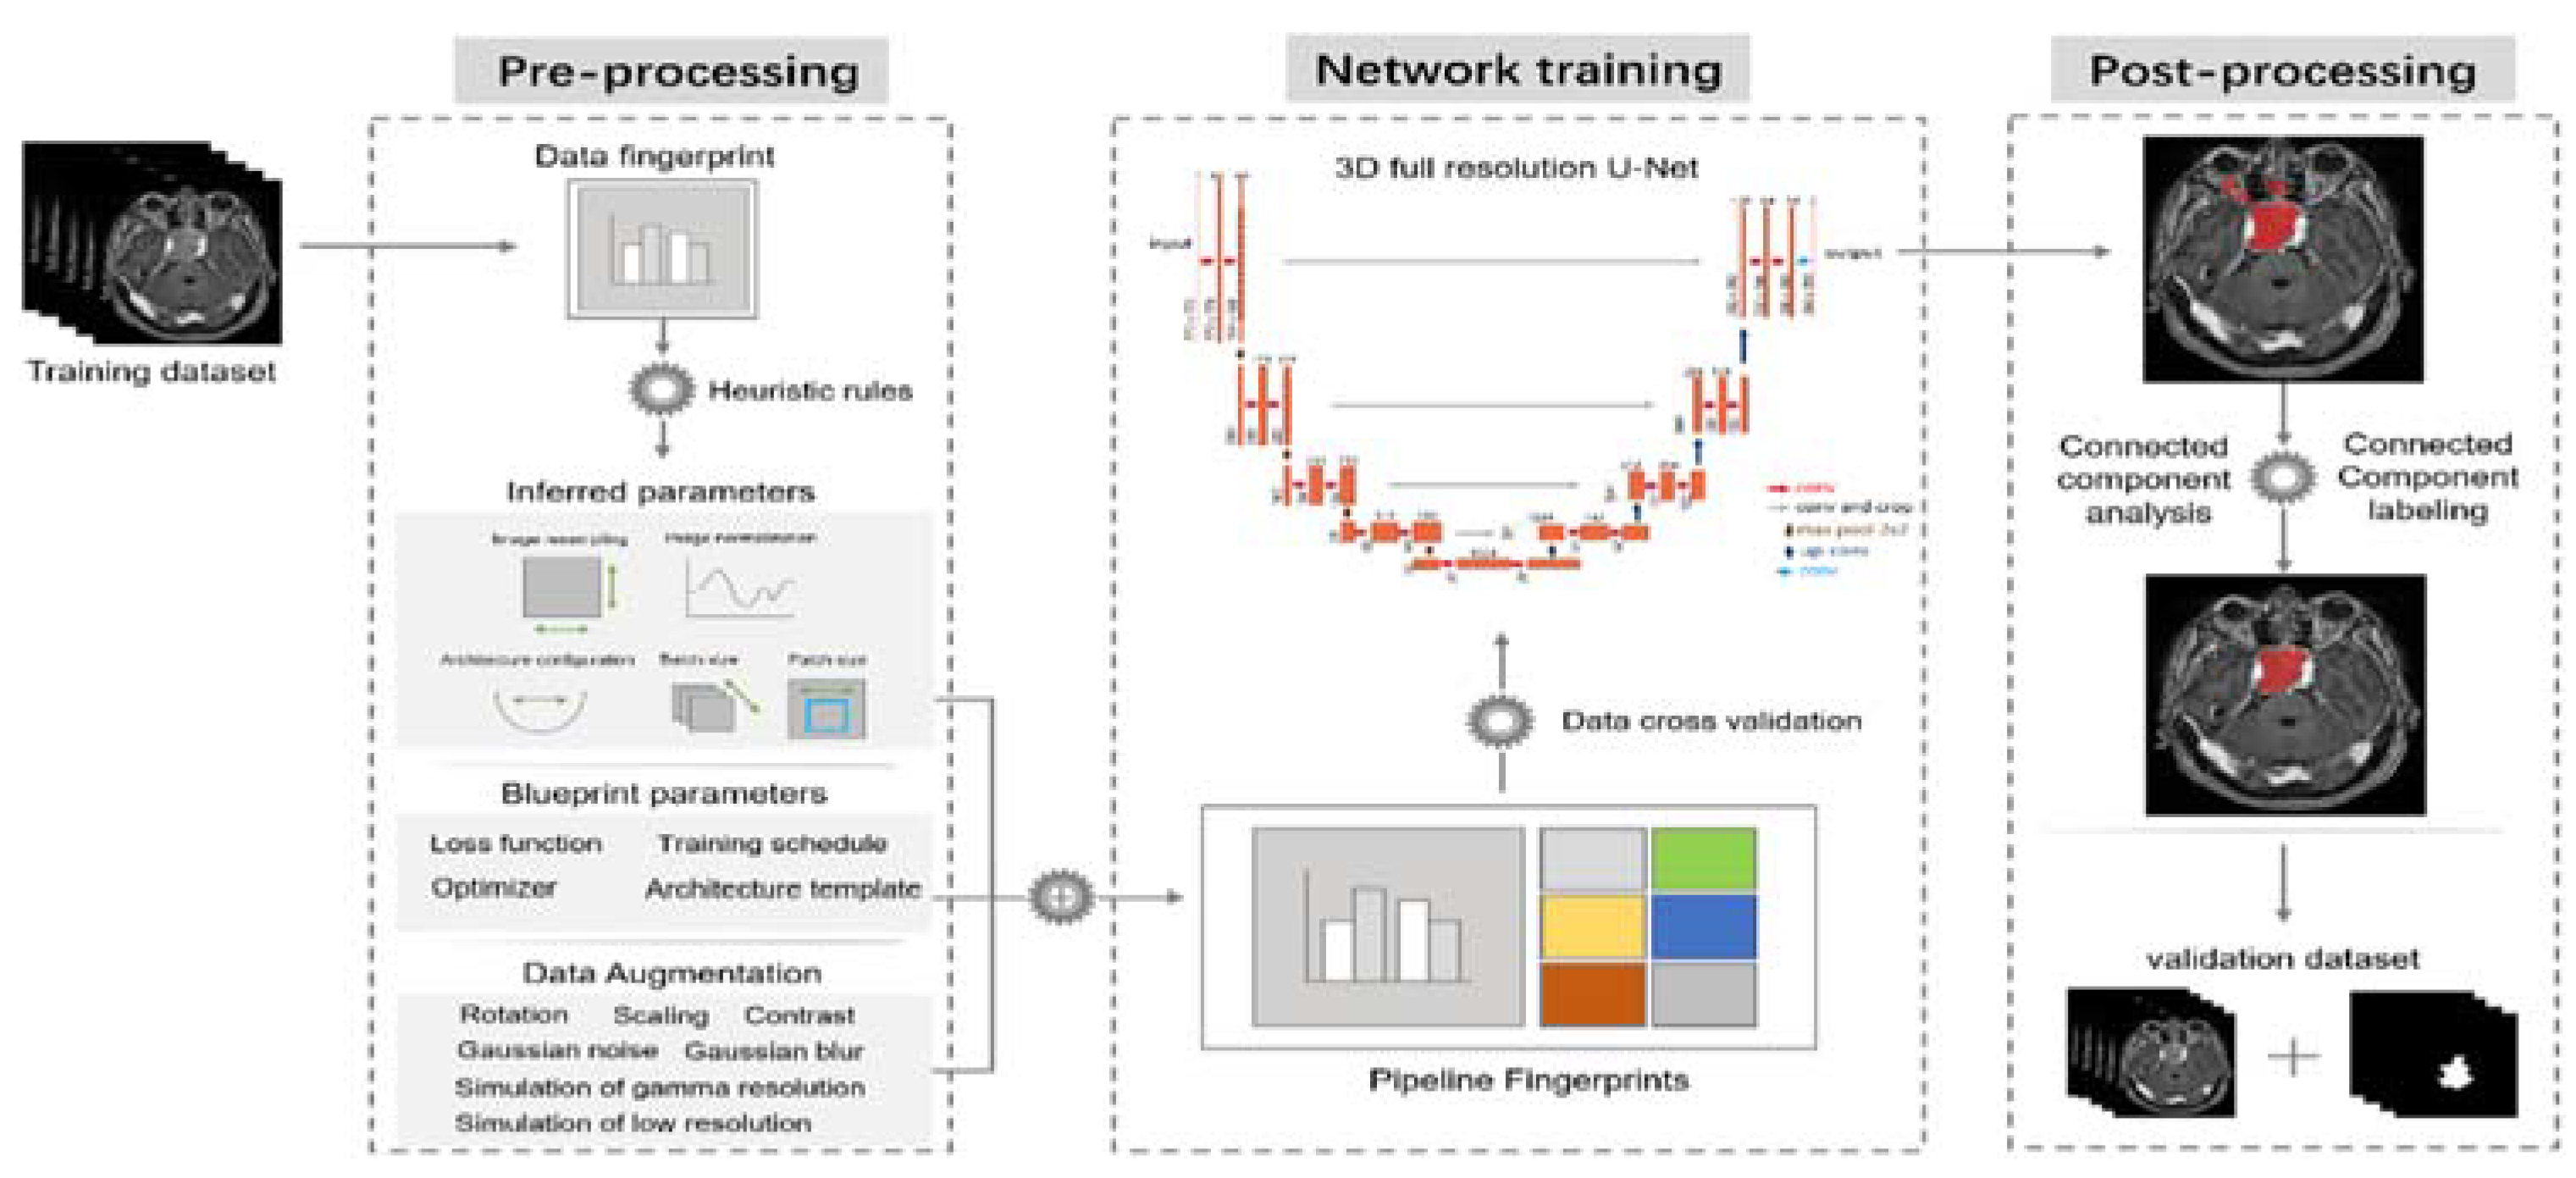

2.4. nnU-Net Framework

2.5. Study Design